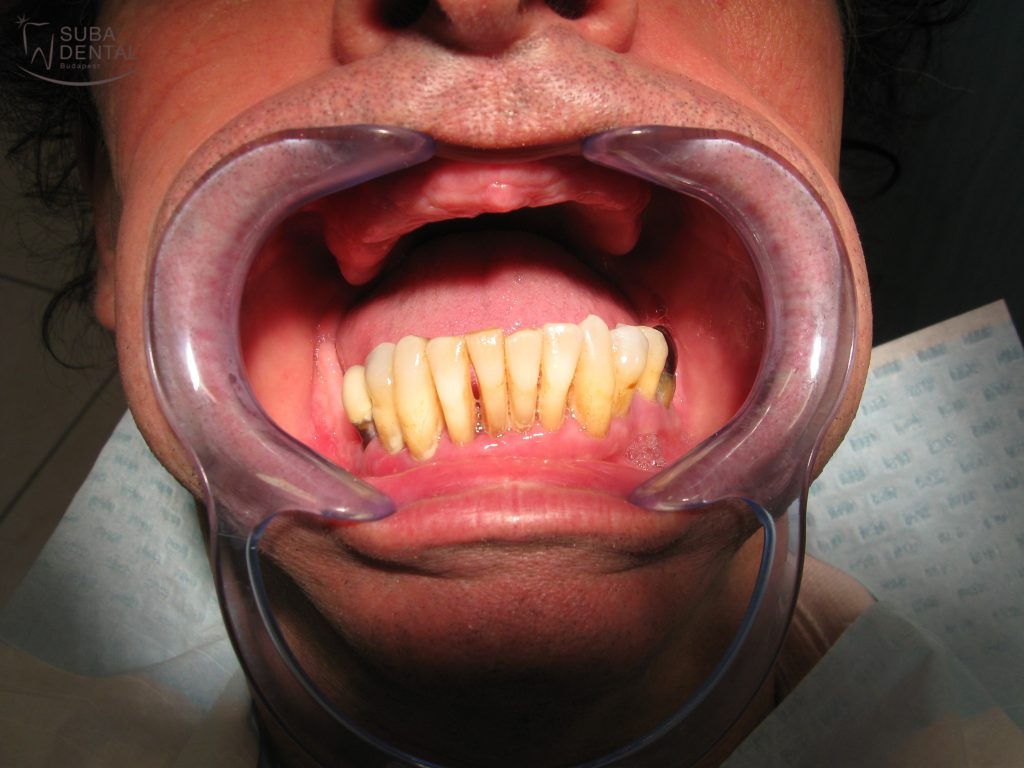

Az alsó fogak, melyeken jól látszik a fogkő és a visszahúzódott fogíny

Páciensünk fel volt készülve erre a hírre, nem érte váratlanul. Átbeszéltük a további fogpótlási lehetőségeket, és a stéges fogsor tűnt számára a legrokonszenvesebbnek. A fix/ rögzített pótlás a nagyfokú csontpusztulás miatt csontpótlás nélkül valóban nem megoldható, de ettől el is zárkózott. Viszont állcsontonként 4 implantátum beültetésének az előzetes vizsgálatok szerint nincs akadálya. Természetesen 100%-os kezelésitervet csak a fogak eltávolítása után 3 hónappal készülő CBCT (Cone beam computed tomography) alapján tudunk felállítani.